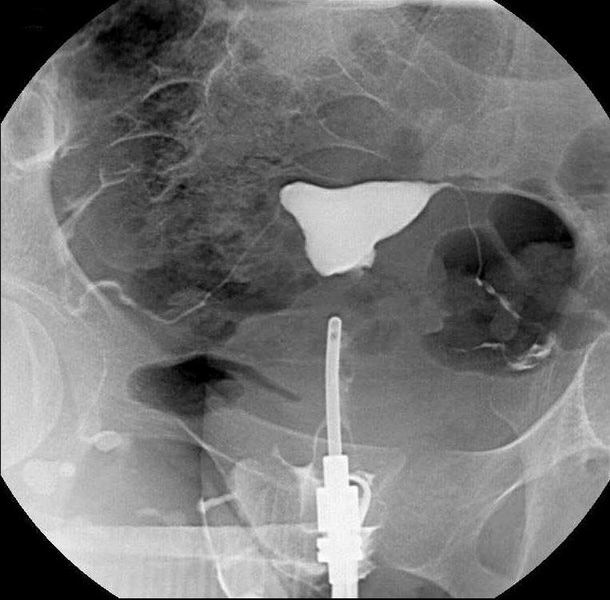

Cystografie